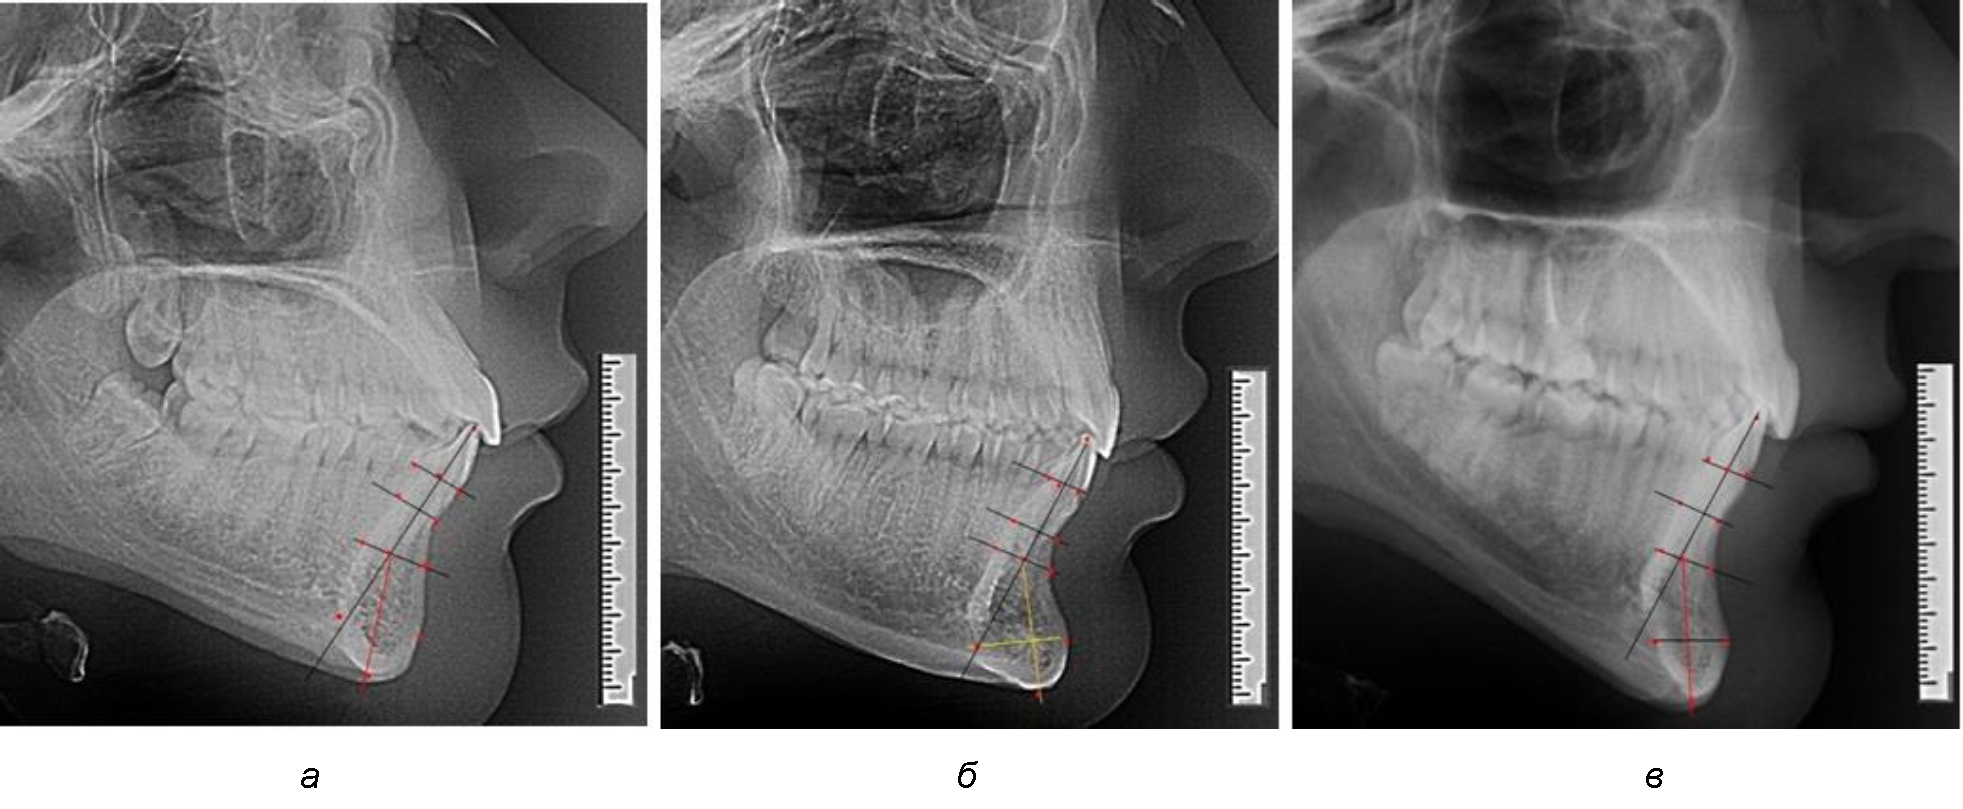

Варианты резцовых сегментов нижней челюсти различные как по ширине, так и по высоте, а также по расхождению положения апикальных точек по Downs и Schwarz представлены на рис. 4.

Рис. 4. Особенности нижнечелюстного резцового сегмента на ТРГ у людей при среднем (а), широком (б) и узком (в) вариантах

Типологические варианты подбородочного выступа, различающиеся по ширине, высоте и расположению апикальных точек, необходимо учитывать в клинике ортодонтии при проведении диагностических мероприятий. Протокольные точки для построения эстетических линий, исходящие из выступающей точки подбородка (Рog – погонион), не всегда могут быть объективным критерием диагностики, что объясняется различной выпуклостью переднего отдела подбородочного выступа. Точки апикального базиса по Шварцу и Даунсу находятся в различных местах подбородка и не всегда совпадают, что требует пояснения при выборе ориентиров. Кроме того, вариабельность сагиттальных размеров зубоальвеолярной части резцового сегмента позволит опти-мизировать методы перемещения резцов в переднее-заднем направлении и определяют костный биотип альвеолярной части нижней челюсти в анализируемой области.

При аномалиях окклюзии в сагиттальном направлении и характерных для них различных вариантах протрузионного и/или ретрузионного патологического положения передних зубов, как правило, сопровождается изменениями параметров подбородочного выступа. Учитывая многообразие форм аномалий окклюзии, параметры подбородочного выступа вариабельны как по сагиттали, так и по трансверсали.

Нередко отмечается деформация подбородочного выступа и различное его положение по отношению к зубоальвеолярной части сегмента. При мезиальной окклюзии нередко нижняя подбородочная точка смещается кзади по отношению к условной срединной вертикали нижнего резца, а при дистальной окклюзии отмечается компенсаторное отклонение подбородка кпереди (рис. 5).

Рис. 5. Особенности нижнечелюстного резцового сегмента на ТРГ у людей при мезиальной (а) и дистальной (б) окклюзии

Кроме того, так же как и у людей с физиологической окклюзией, определялось различие в положении апикальных точек Downs и Schwarz, что, по нашему мнению, может определять тактику лечения патологических форм протрузии/ретрузии резцов с учетом биотипа костной ткани.